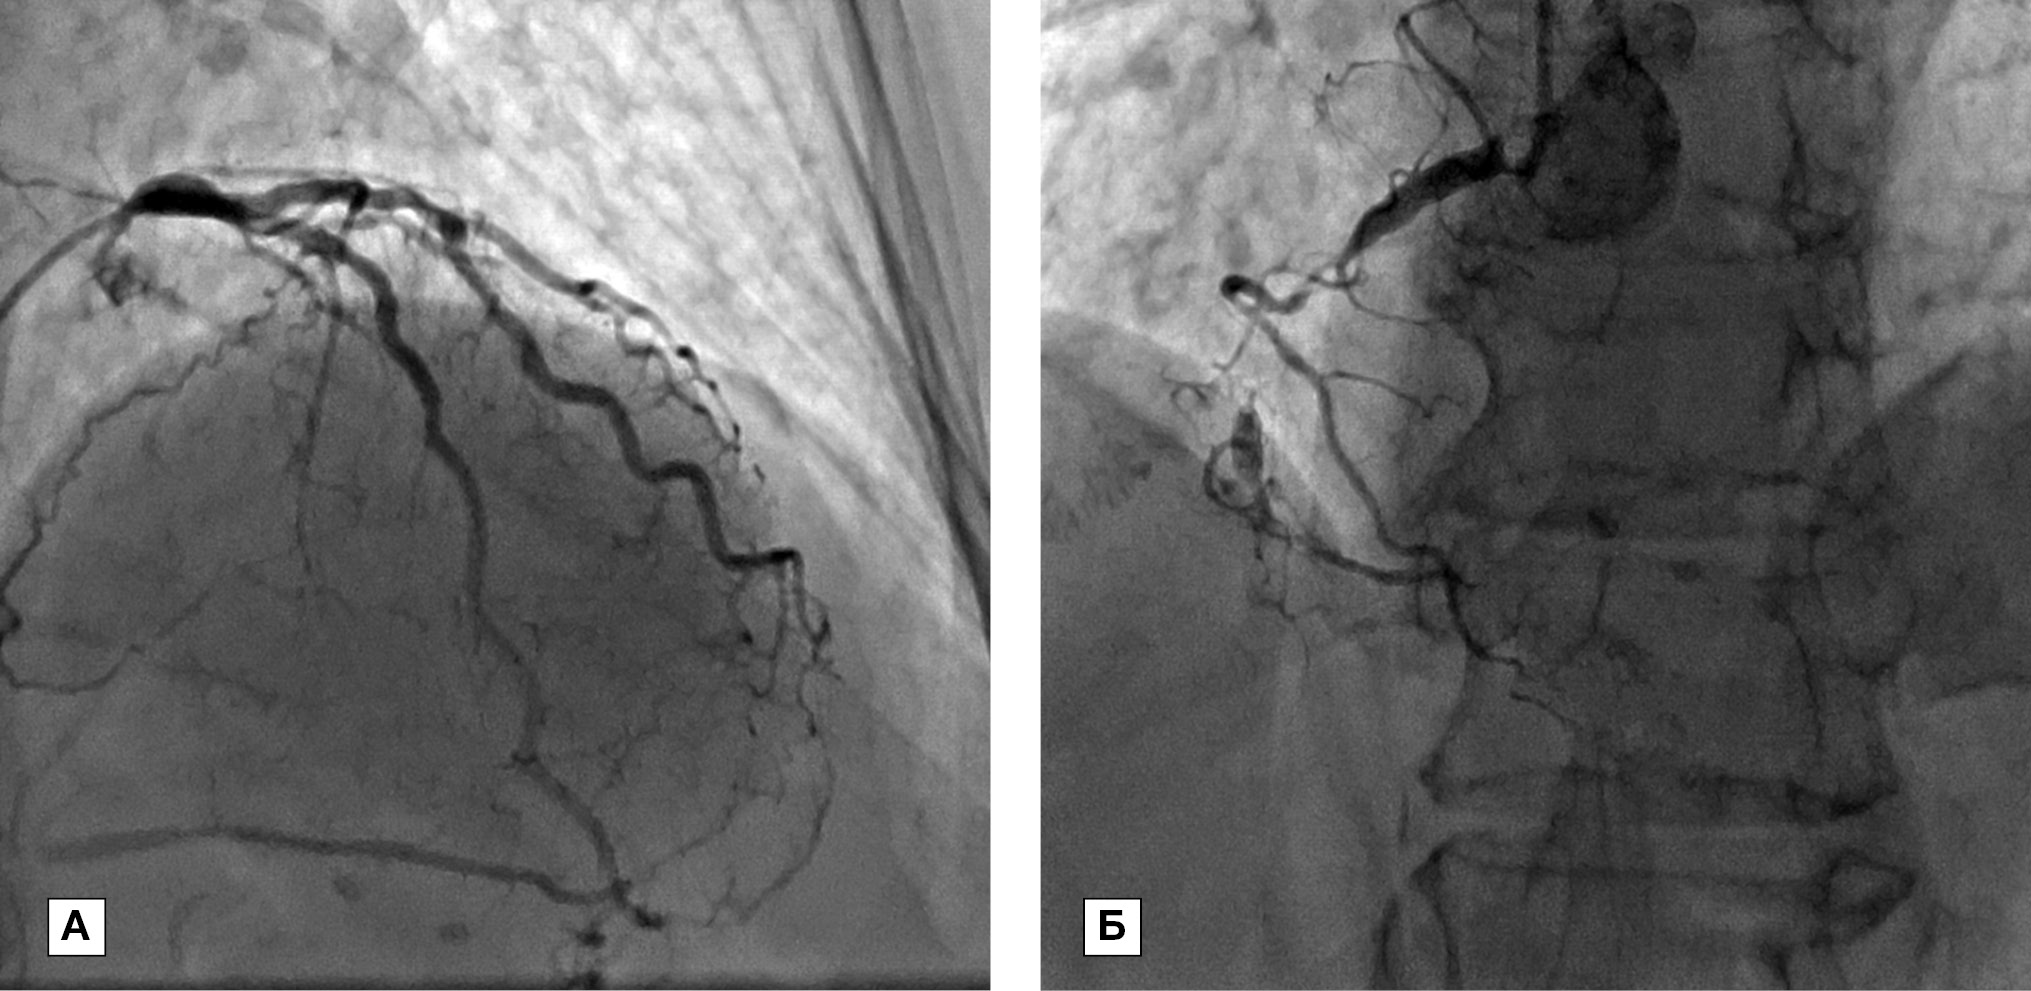

Мать больного (на момент обследования — 67 лет) длительно страдает ишемической болезнью сердца, стенокардией напряжения III функционального класса, артериальной гипертензией, сахарным диабетом. По данным коронарной ангиографии выявлено многососудистое поражение коронарных артерий (рис. 2 А, Б). В анализе крови от 23.11.2018 (без липидснижающих препаратов): общий холестерин 10,0 ммоль/л, холестерин ЛВП 1,74 ммоль/л, холестерин ЛНП 6,7 ммоль/л, триглицериды 3,46 ммоль/л. ЭхоКГ от 24.11.2015: межжелудочковая перегородка 1,3 см, задняя стенка левого желудочка 1,2 см, фракция выброса ЛЖ 55%, умеренное расширение полостей предсердий. Таким образом, у матери больного также имеются признаки семейной гиперлипидемии.

Рис. 2 А, Б. Данные коронароангиографии матери больного М.